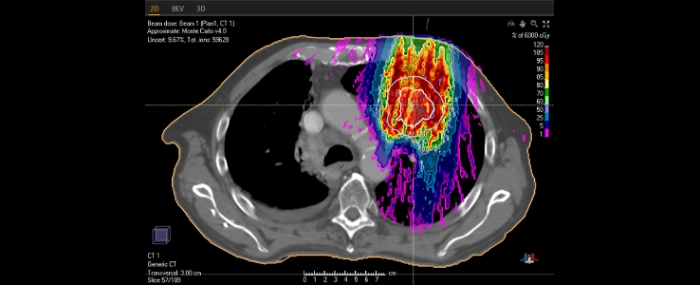

Alla centren får den senaste versionen av RayStation, som inkluderar innovativa funktioner som snabb optimering och dosberäkning med Monte Carlo för pencil beam-skanning (PBS), möjligheten att kombinera PBS med aperturer, och robust optimering/4D-CT-optimering för planering av proton- och koljonterapi. Alla inköp omfattar såväl kliniska licenser som licenser för forskning.